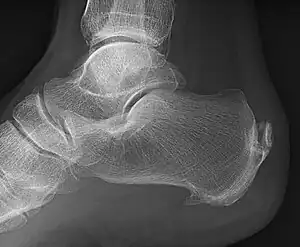

![]() | |

| A radiograph showing osteophytes on the posterior and inferior aspects of the calcaneus | |

A calcaneal spur (also known as a heel spur) is a bony outgrowth from the calcaneal tuberosity (heel bone).[1] It generally, has no effect on a person's daily life.

When a foot is exposed to constant stress, calcium deposits build up on the bottom of the heel bone. However, repeated damage can cause these deposits to pile up on each other, causing a spur-shaped deformity, called a calcaneal (or heel) spur.[2] It is typically detected by x-ray.[3] It is a form of exostosis.

An inferior calcaneal spur is located on the inferior aspect of the calcaneus and is typically a response to plantar fasciitis over a period, but may also be associated with ankylosing spondylitis (typically in children). A posterior calcaneal spur develops on the back of the heel at the insertion of the Achilles tendon.[2]

An inferior calcaneal spur consists of a calcification of the calcaneus, which lies superior to the plantar fascia at the insertion of the plantar fascia. A posterior calcaneal spur is often large and palpable through the skin and may need to be removed as part of the treatment of insertional Achilles tendonitis.[2]